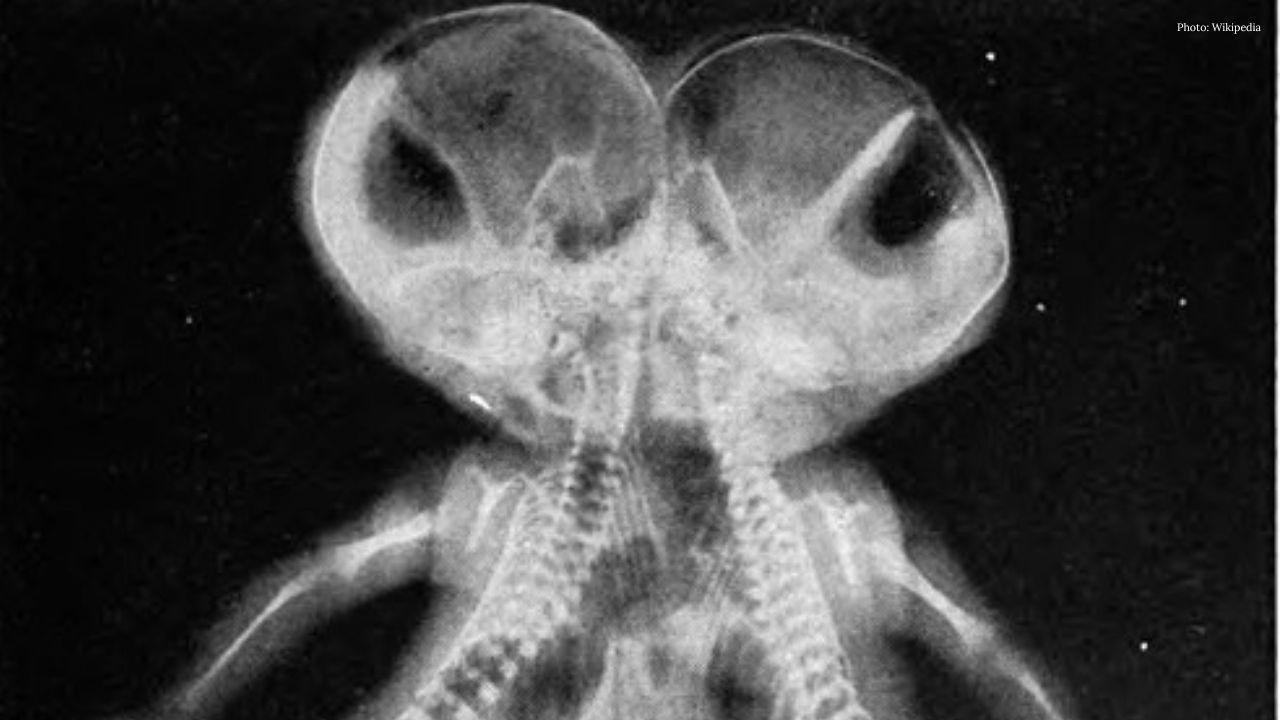

Pakistani Conjoined Twins Arrive in Saudi Arabia for Surgery Assessment

Pakistani twins Sufyan and Yusuf reach Riyadh for evaluation before possible separation s…